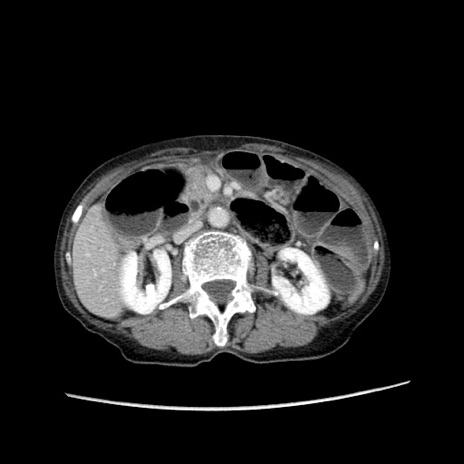

症例25(横断像)

【症例】80歳代女性

【主訴】胸のつかえ感

【現病歴】約9時間前に食後から胸のつかえた感じあり、嘔吐あり、来院。

【既往歴】胃癌(全摘)、胆摘、虫垂炎

【身体所見】心窩部に圧痛あり、反跳痛なし。

【データ】WBC 5700、CRP 0.05